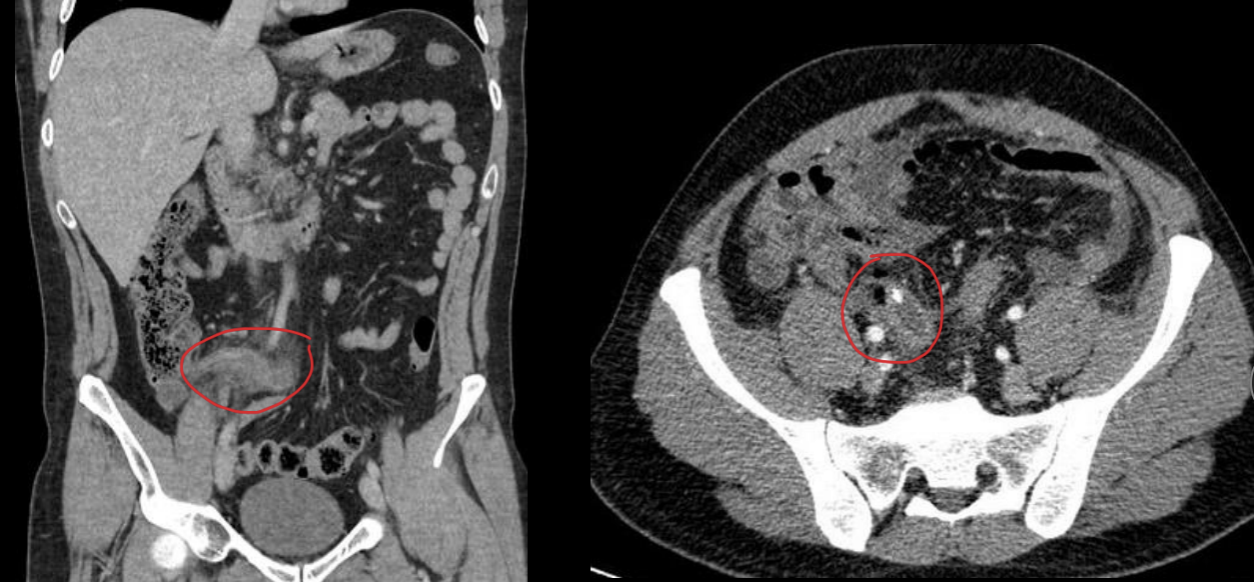

15

Q

A

Grasa sucia con inflamación apéndice